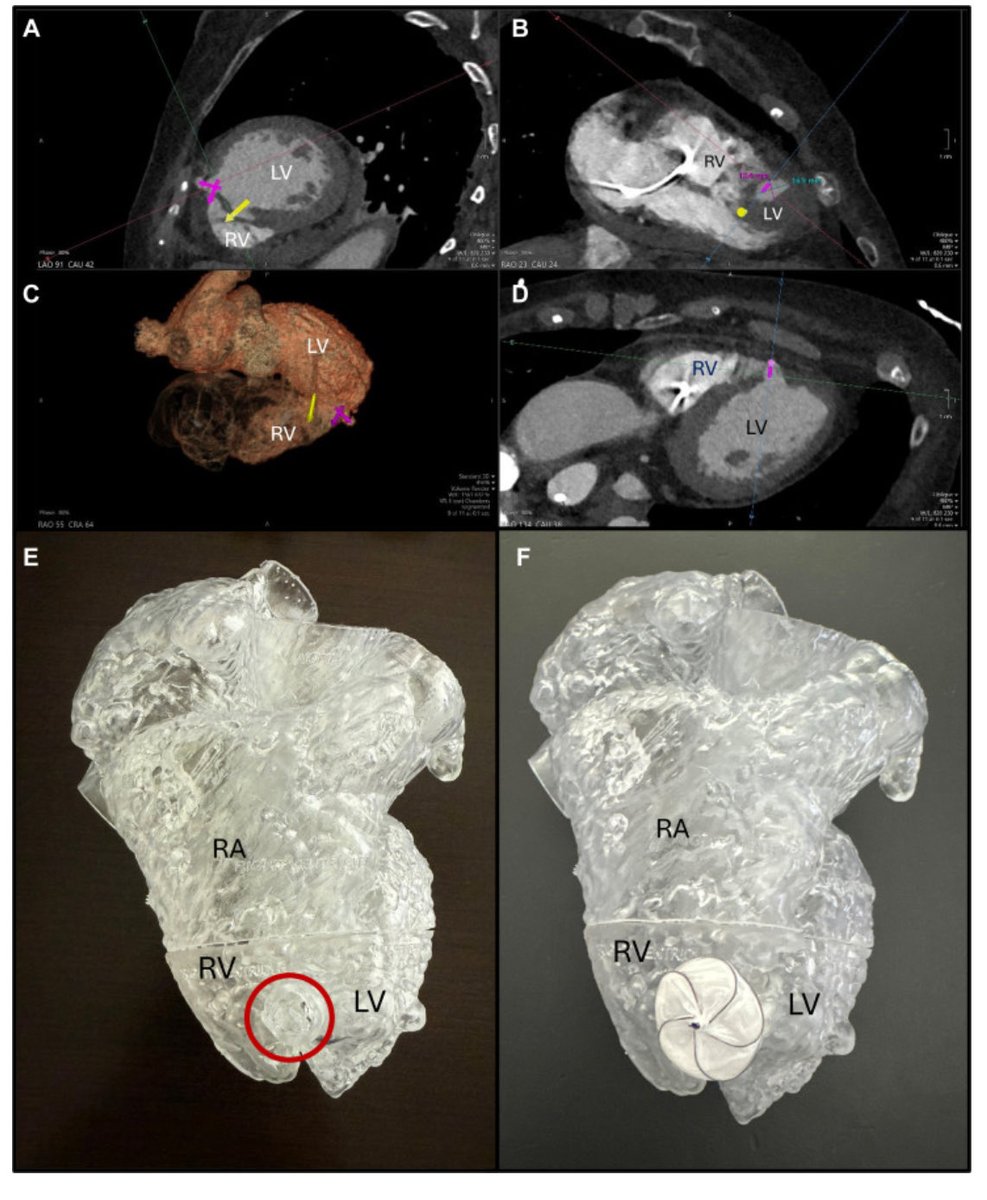

Heroic save following AMI Shock in a patient with double insult: ventricular pseudoaneurysm and VRS. #innovation #heartteam @NCHRooneyHeart @JACCJournals #Shock #AMI @ACCinTouch @JACCJournals @DeeDeeWangMD @PU84 @DrBrianSolomon sciencedirect.com/science/articl…